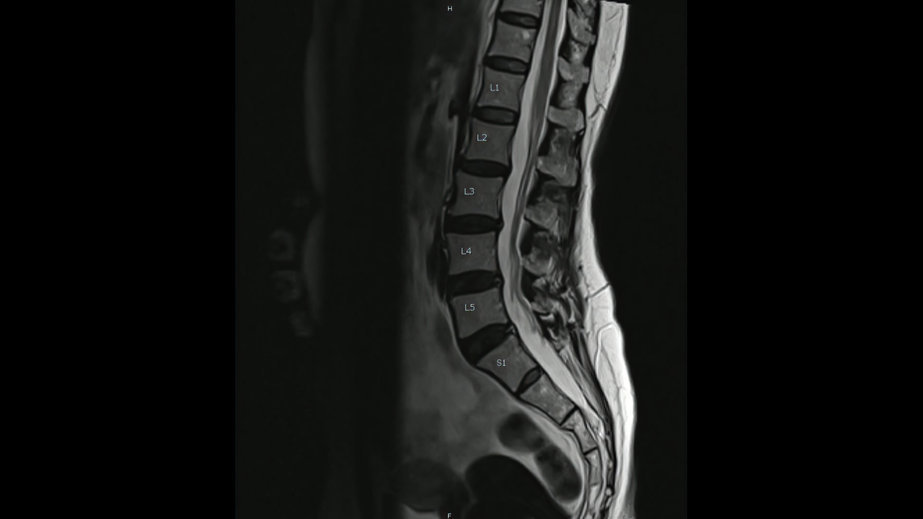

MRIは筋肉、腱、靭帯、軟骨、椎間板などの損傷や炎症

レントゲンやMRIでは本当の原因は見つかりません。

画像検査では筋肉硬化、筋膜の癒着や自律神経の状態はわかりません。検査、カウンセリング、施術など、アプローチ方法が異なる事で改善効果が高くなります。